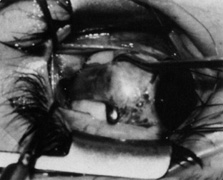

Step 1. The lateral rectus muscle is isolated through either a limbal (Fig. 1) or fornix incision. The muscle is dissected free of intermuscular septum and check ligaments for a distance of approximately 15 mm posterior to its insertion. When a fornix approach is used, the procedure can be performed through a single inferior temporal incision; however, making a second superior temporal fornix incision facilitates reattachment of the superior arm of the muscle.

Fig. 1. The lateral rectus muscle is isolated through a limbal incision and dissected free of intermuscular septum and check ligaments for a distance of approximately 15 mm posterior to its insertion.